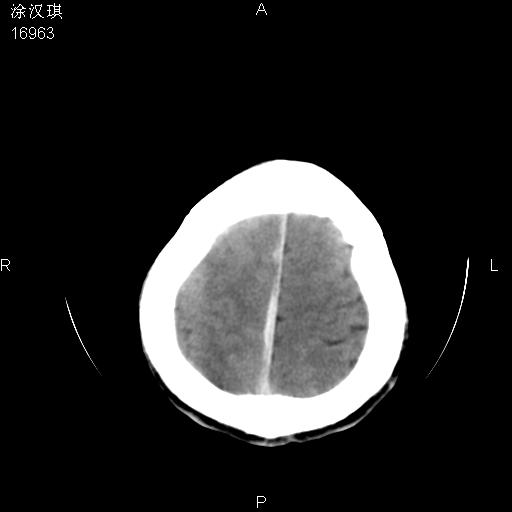

以下是引用chinazhouhua在2008-5-1 12:06:00的发言:[br]影像上来看,这是个典型的硬膜下血肿,包括右侧额颞部、大脑镰下、小脑幕下,而且在右侧额颞顶枕部、大脑镰下没看到高密度出血向脑沟内延伸,但是小脑幕下硬膜下有时候和蛛血不是很好鉴别,而且硬膜下很多时候伴有蛛血,往往在复查的时候出来,所以这种病人还是应该考虑硬膜下血肿伴有蛛血。

以下是引用zsl6918在2008-5-1 15:34:00的发言:[br]本病例主要表现为急性硬膜下血肿。